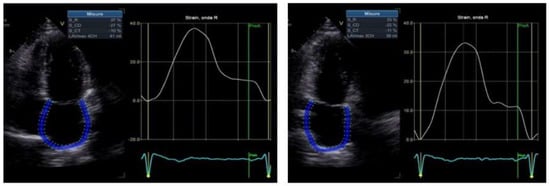

| LV GLS 2D (%) | 19.7 ± 1.6 | 17.6 ± 4 | 12.5 ± 3.9 | p = 0.11 | p = 0.01 |

| Apical–basal strain ratio | 1.33 ± 0.20 | 1.58 ± 0.25 | 3.3 ± 2.1 | p = 0.001 | p = 0.008 |

| Relative apical sparing | 0.62 ± 0.07 | 0.72 ± 0.08 | 1.3 ± 0.6 | p = 0.0039 | p = 0.002 |